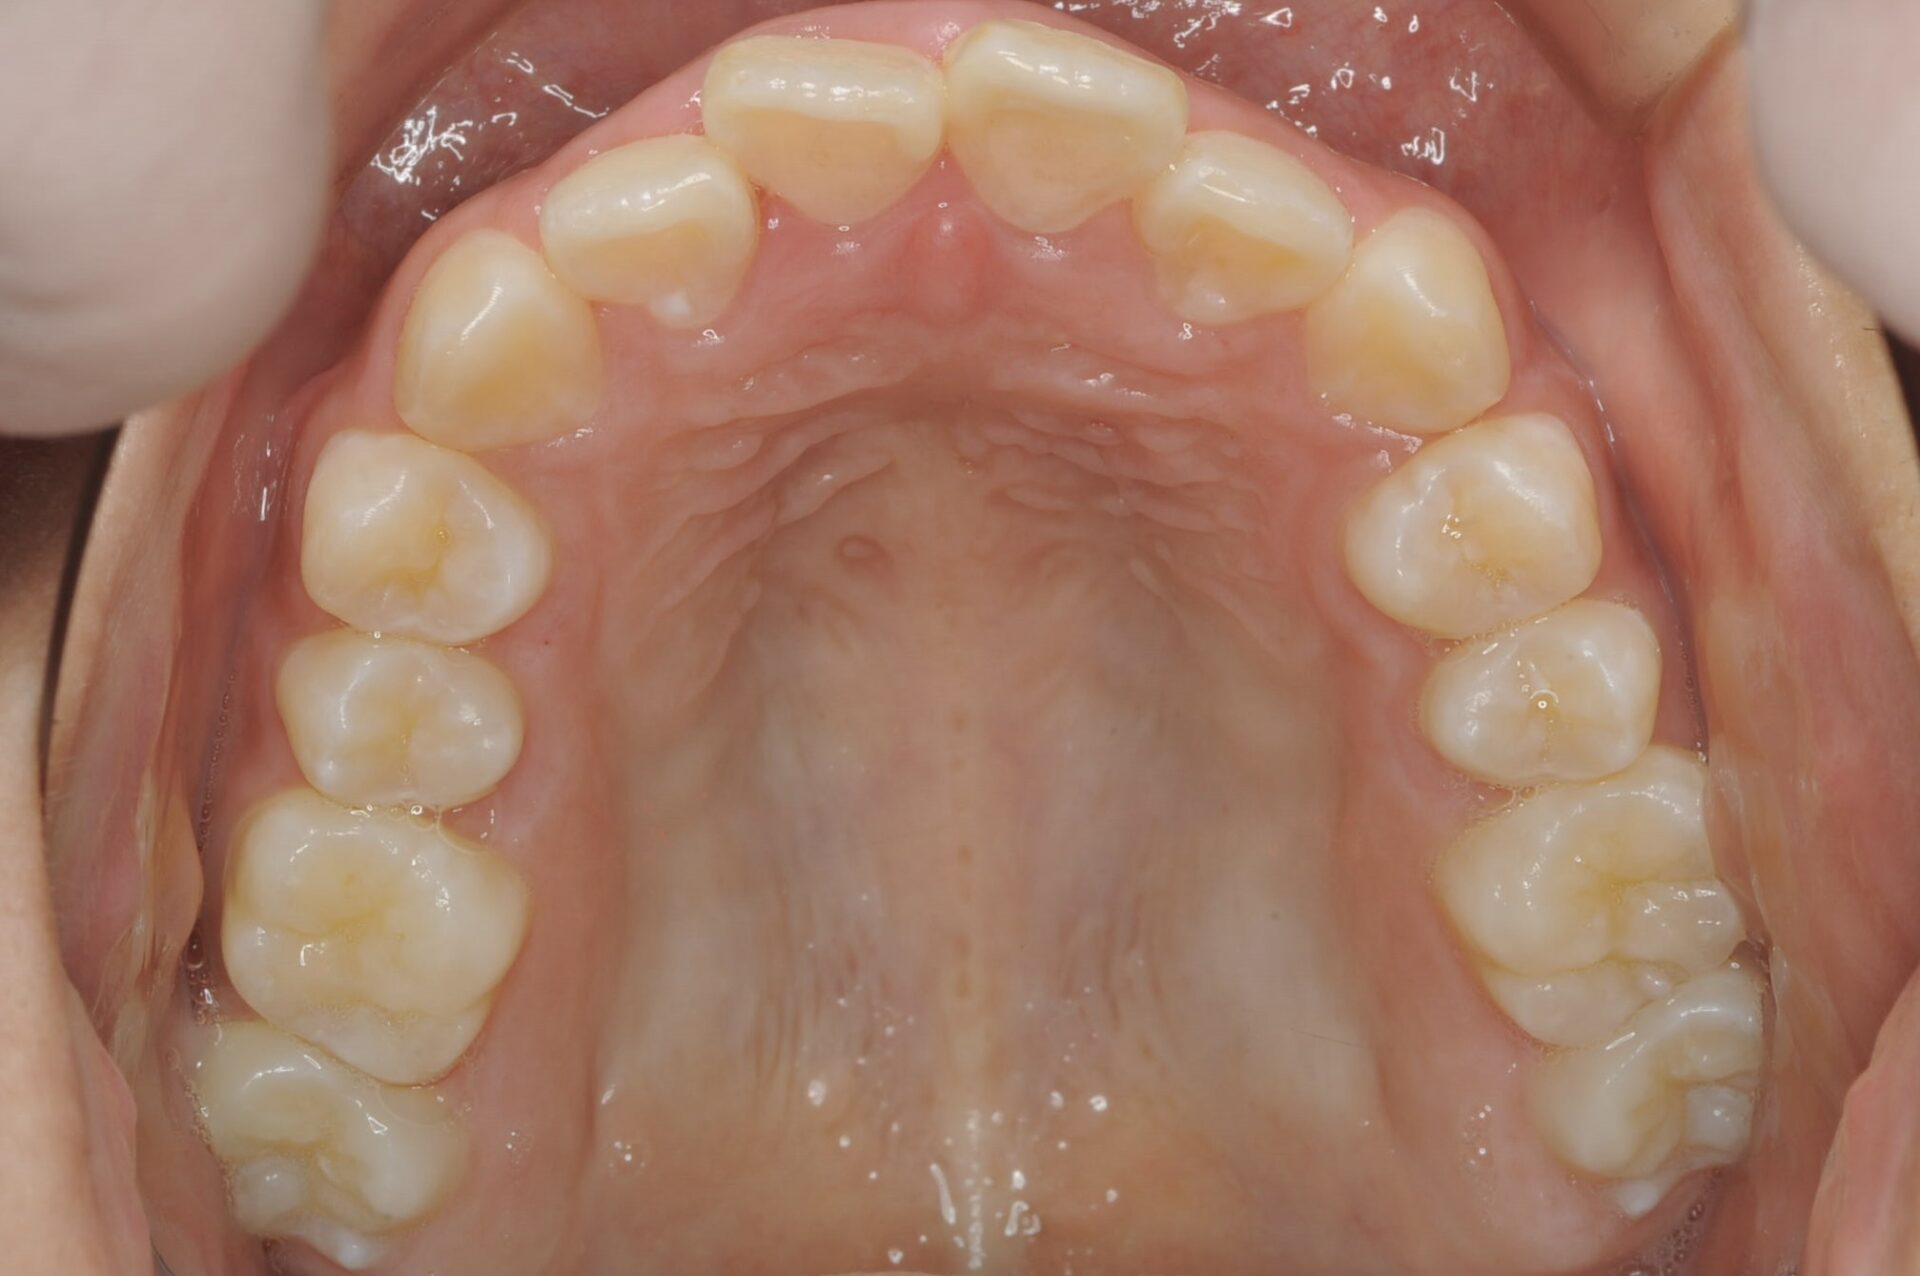

初診時(上顎)

矯正治療スタート時